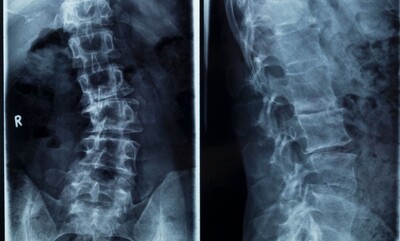

In-House Digital X-Rays